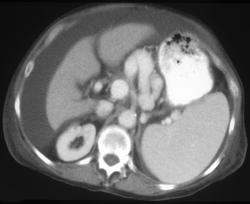

Gastric Lymphoma